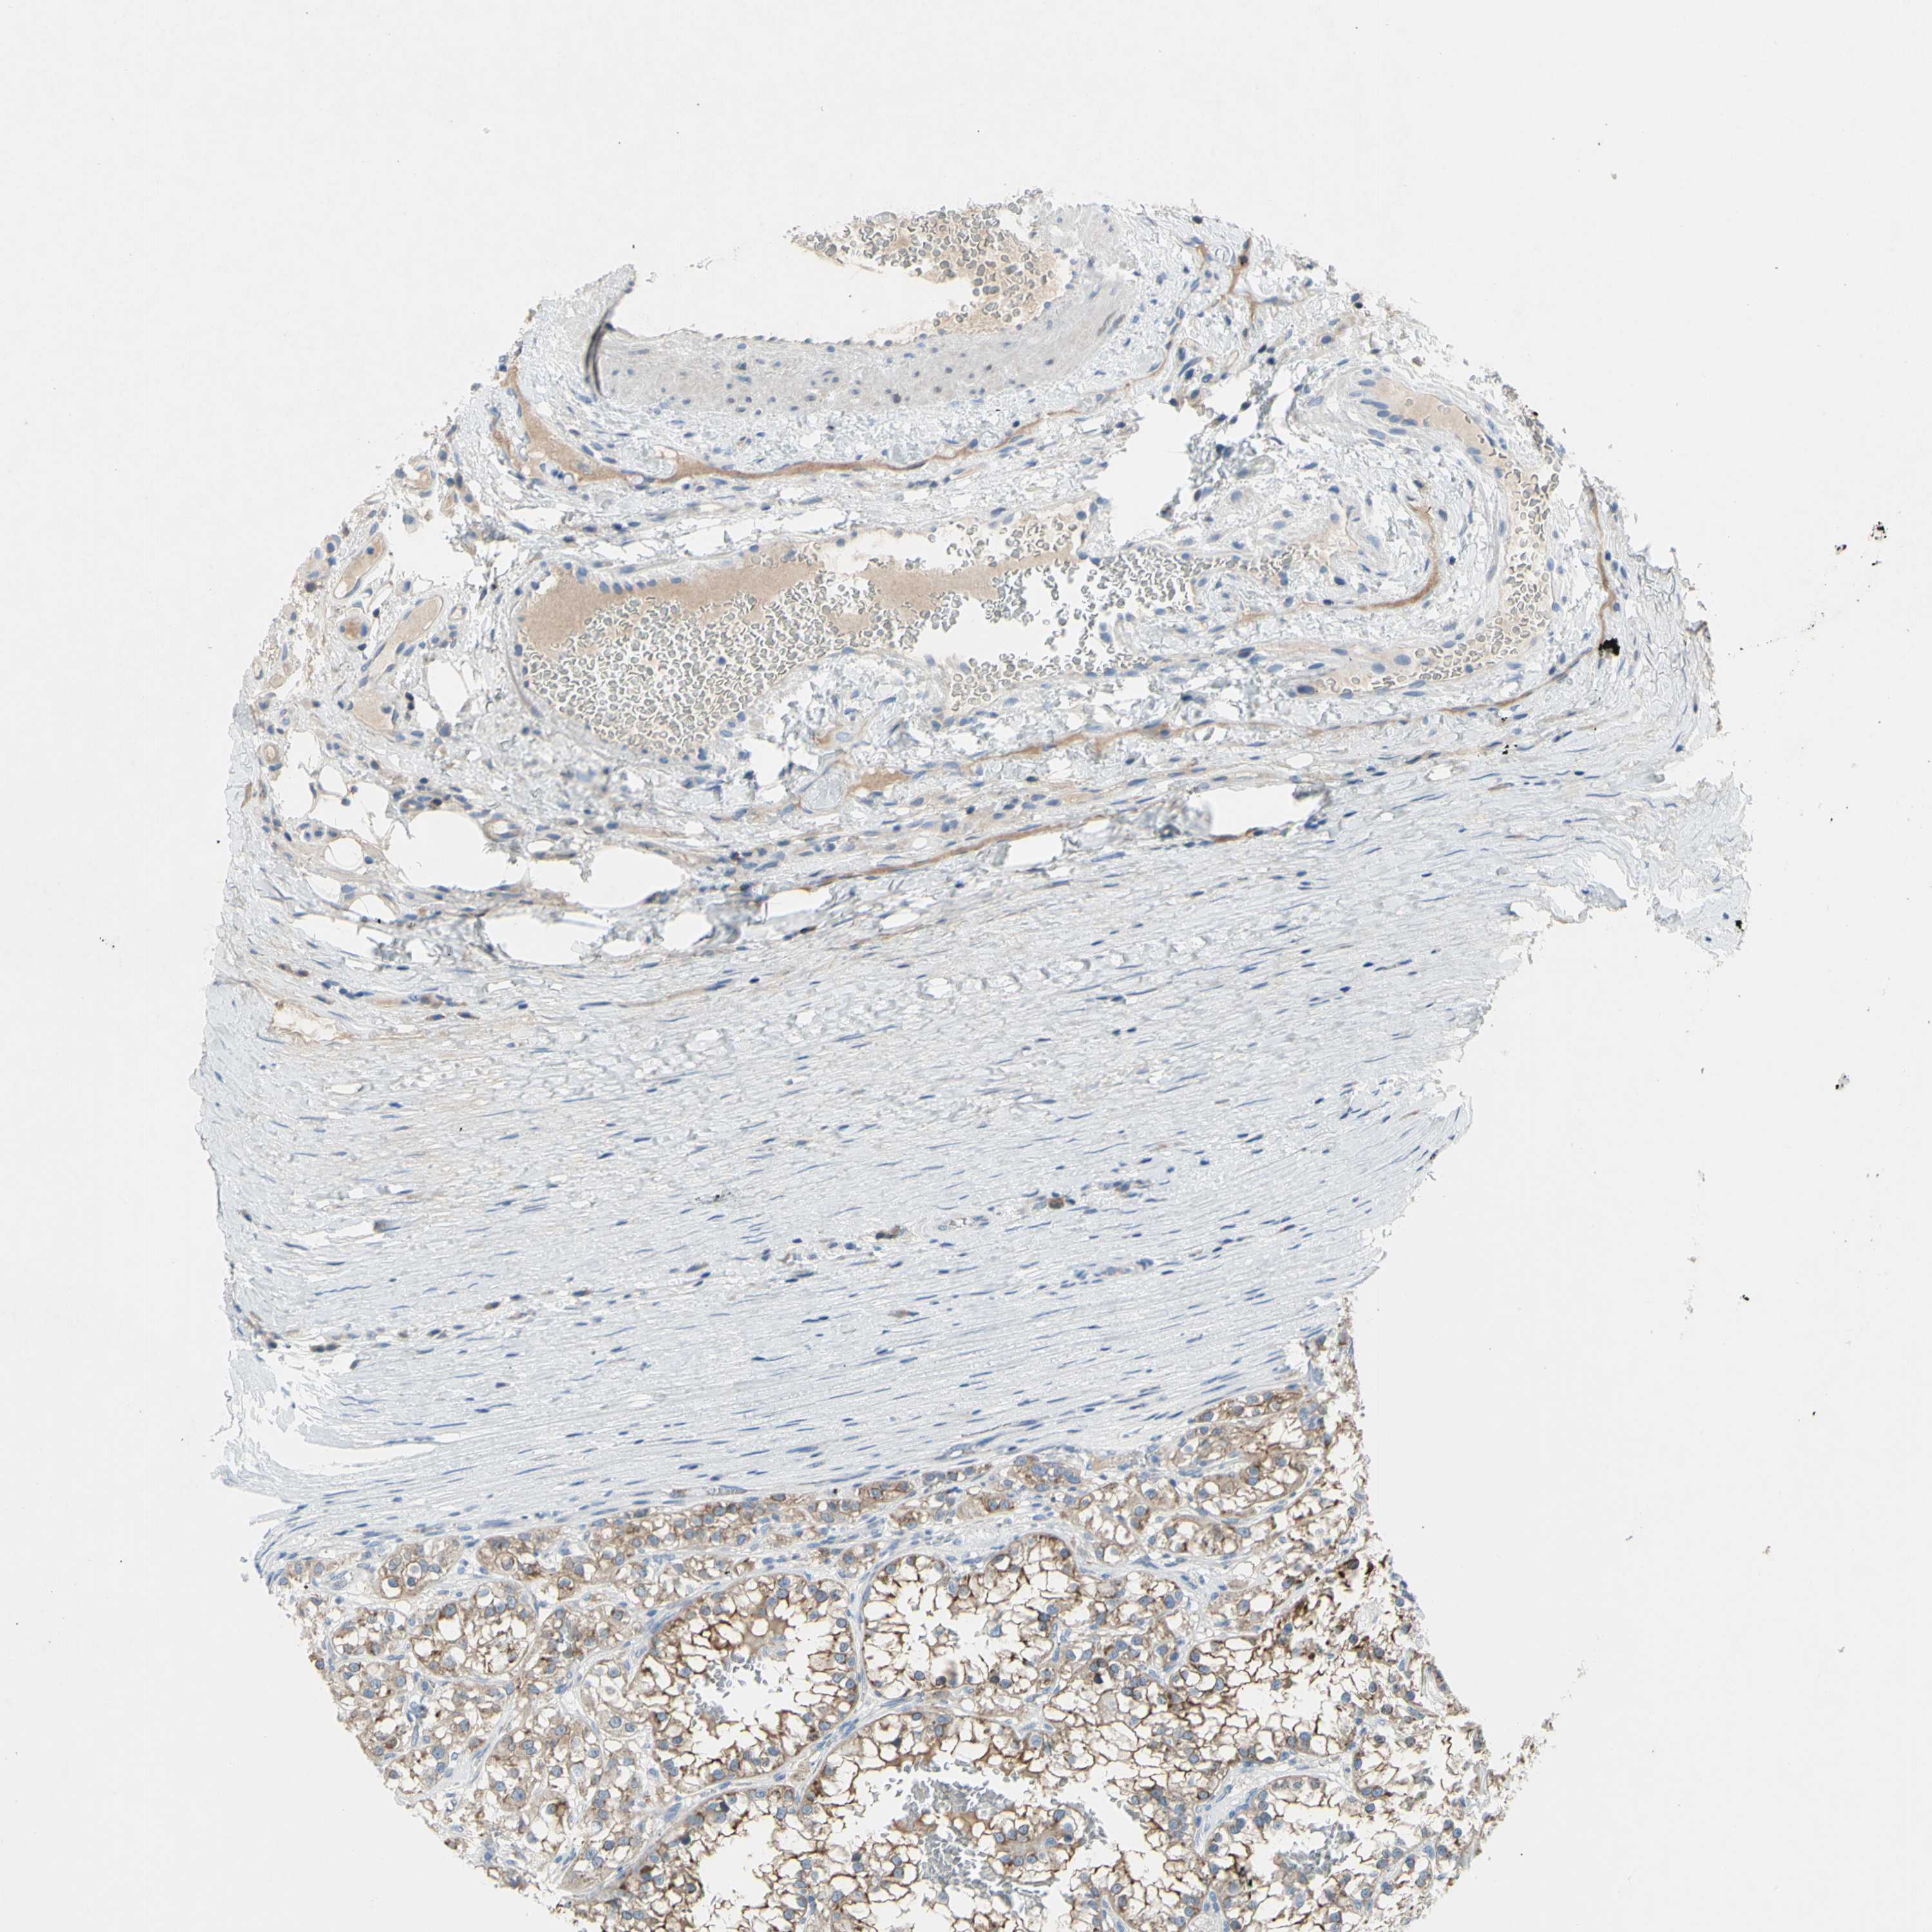

KIDNEY RENAL PAPILLARY CELL CARCINOMA (TCGA) - Interactive survival scatter ploti

The Survival Scatter plot shows the clinical status (i.e. dead or alive) for all individuals in the patient cohort, based on the same data that underlies the corresponding Kaplan-Meier plots. Patients that are alive at last time for follow-up are shown in blue and patients who have died during the study are shown in red.

The x-axis shows the expression levels (FPKM) of the investigated gene in the tumor tissue at the time of diagnosis. The y-axis shows the follow-up time after diagnosis (years). Both axes are complimented with kernel density curves demonstrating the data density over the axes. The top density plot shows the expression levels (FPKM) distribution among dead (red) and alive patients (blue). The right density plot shows the data density of the survived years of dead patients with high and low expression levels respectively, stratified using the cutoff indicated by the vertical dashed line through the Survival Scatter plot. This cutoff is automatically defined based on the FPKM cutoff that minimizes the p-score. The cutoff can be changed by dragging the vertical line or by entering a cutoff value in the square labeled "Current cut-off".

Under the Survival Scatter plot the p-score landscape (black curve; left axis) is shown together with dead median separation (red curve; right axis). Dead median separation is the difference in median mRNA expression between patients who have died with high and low expression, respectively. It is calculated as follows: median FPKM expression of dead patients with high expression - median FPKM expression of dead patients with low expression. This is intended to aid the user in visually exploring custom cutoffs and the associated p-scores and dead median separation.

Individual patient data is displayed and can be filtered by clicking on one or more of the category buttons on the top of the page. Categories describing expression level and patient information include: high, low, alive, dead, female, male and tumor stages. The scale of the x-axis can be toggled between linear and log-scale by clicking on the "x log" button. Mouse-over function shows TCGA ID, patient information and mRNA expression (FPKM) for each patient.

& Survival analysisi

Kaplan-Meier plots summarize results from analysis of correlation between mRNA expression level and patient survival. Patients were divided based on level of expression into one of the two groups "low" (under cut off) or "high" (over cut off). X-axis shows time for survival (years) and y-axis shows the probability of survival, where 1.0 corresponds to 100 percent.

MUC1 is not prognostic in Kidney Renal Papillary Cell Carcinoma (TCGA)